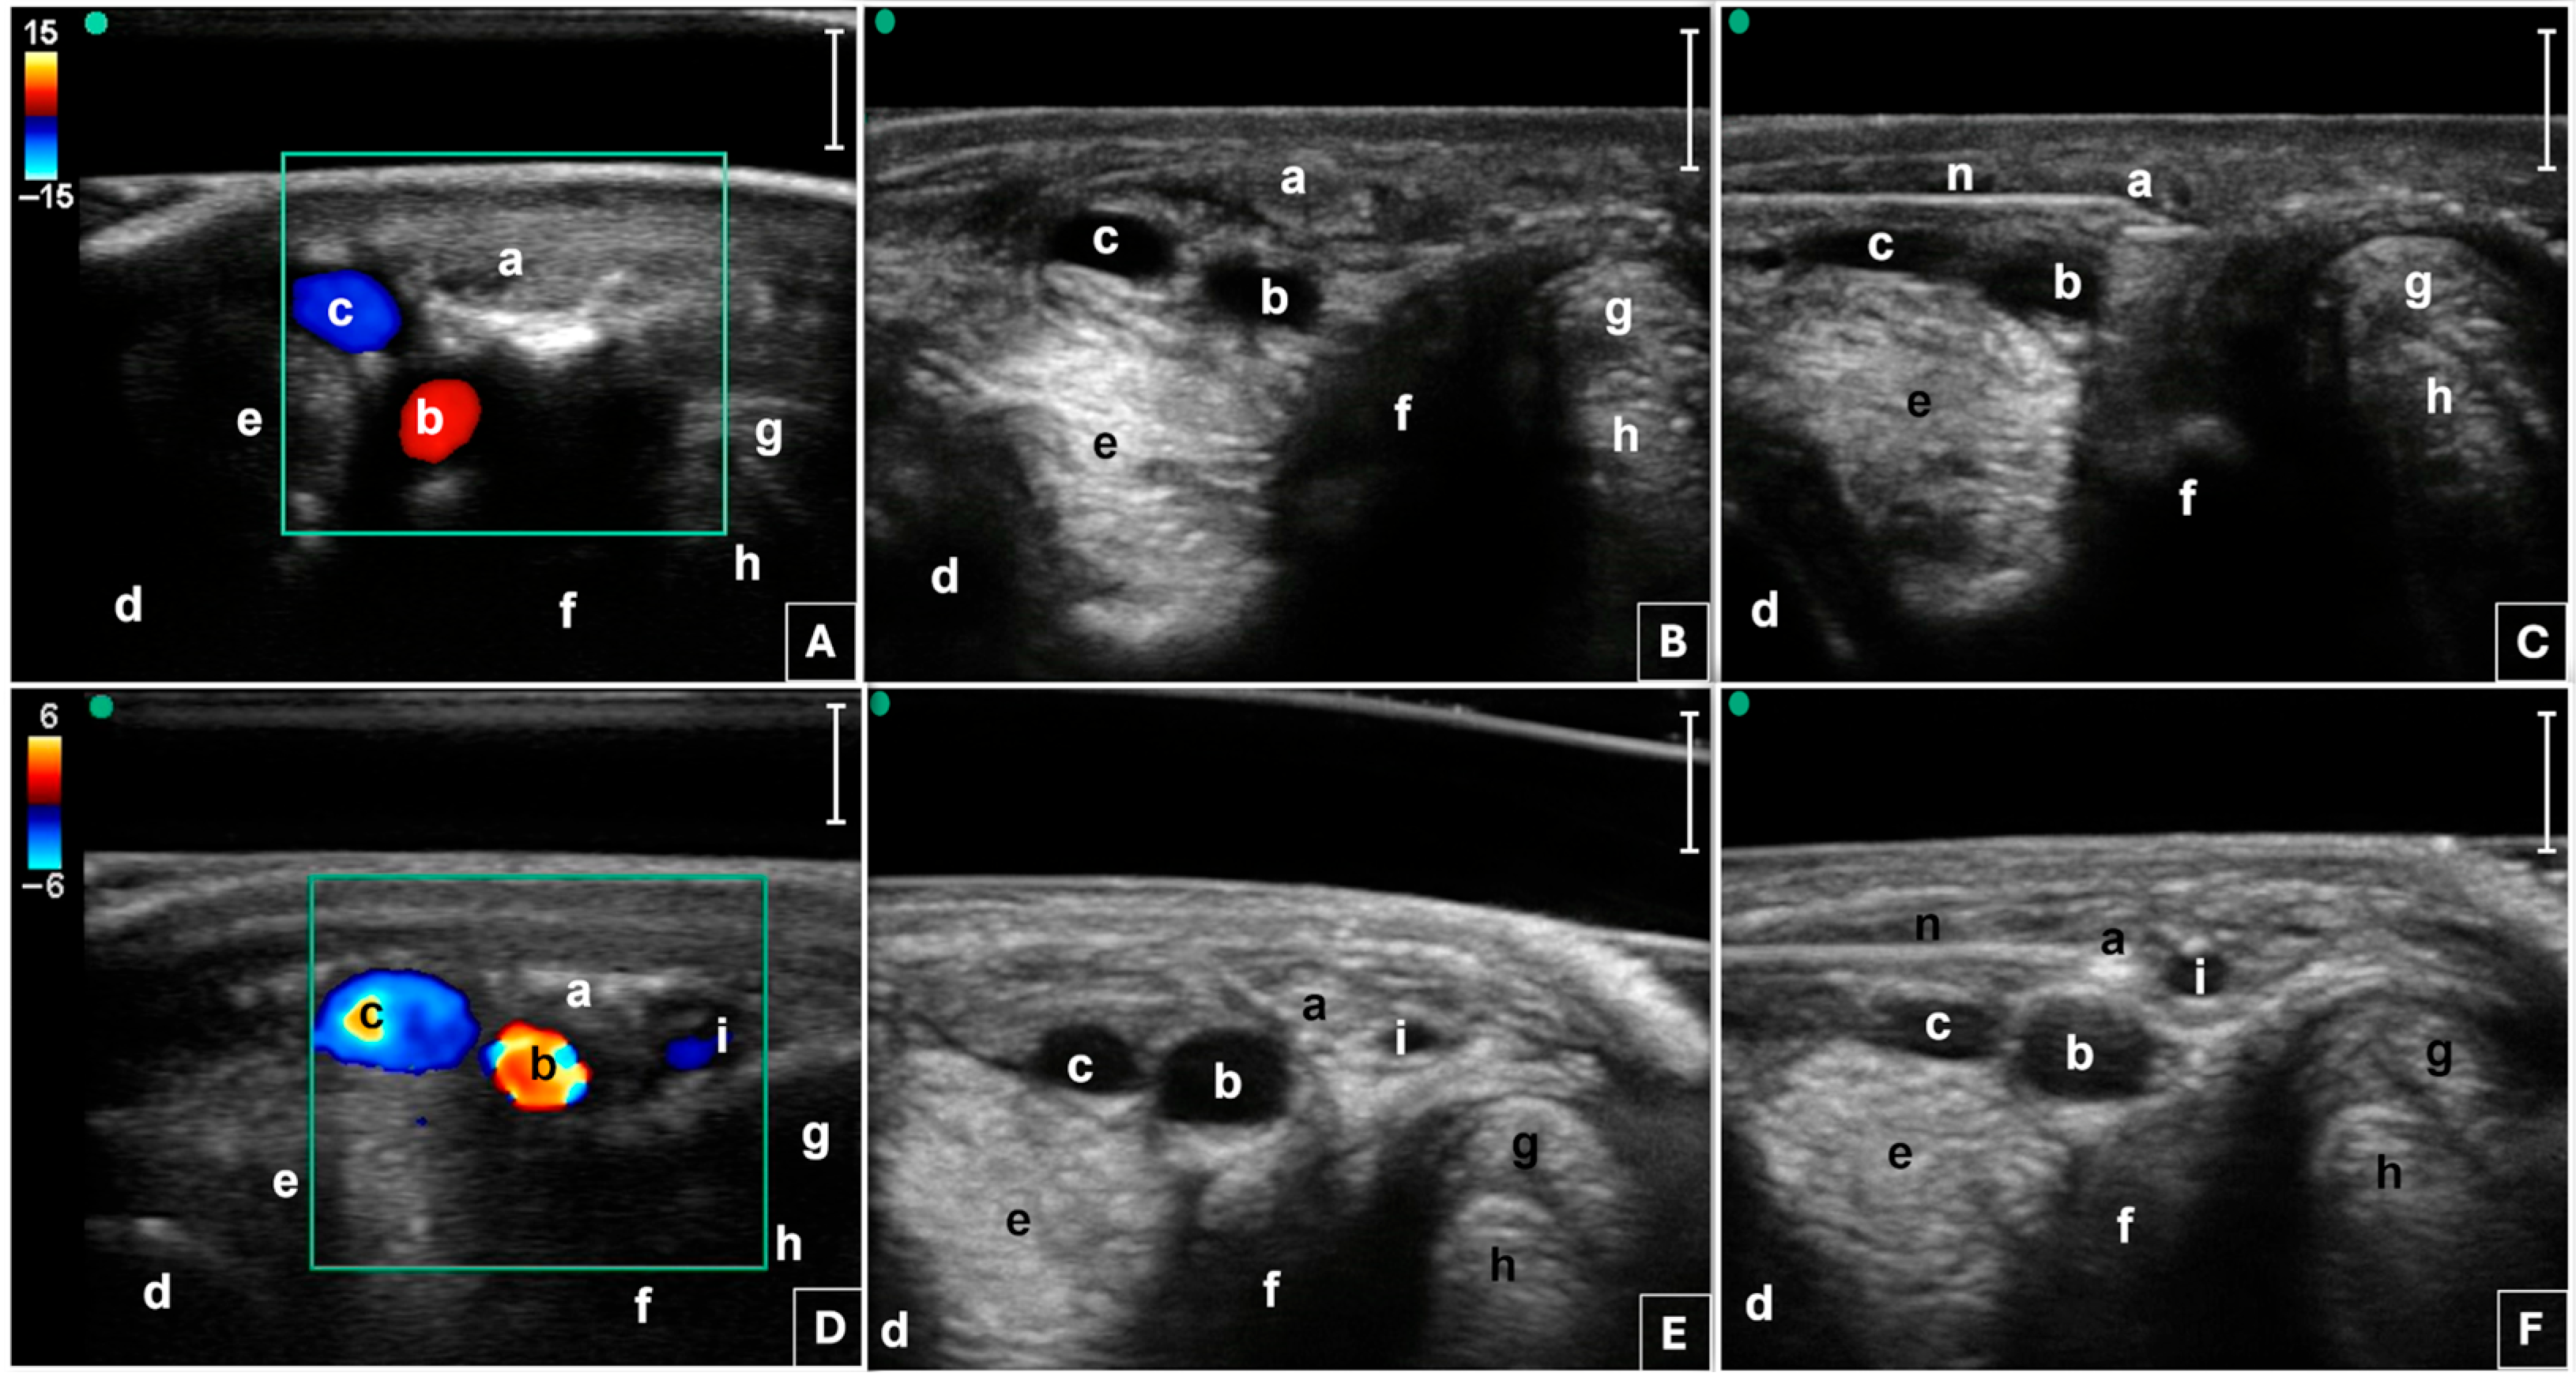

2.3. Radiofrequency Procedure